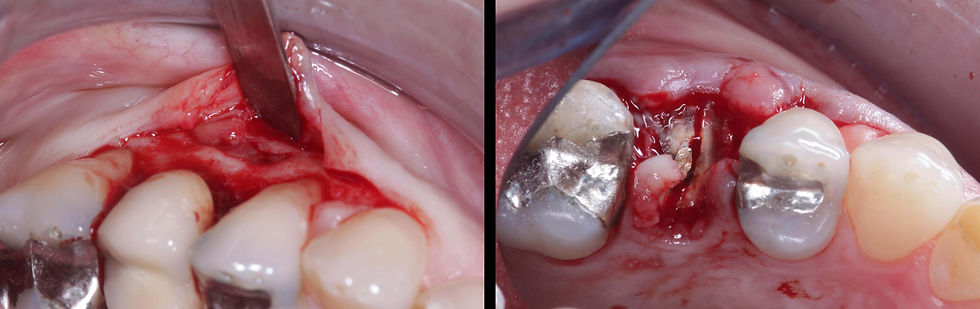

First surgical step: an intrasulcular flap is raised and the root fracture is exposed after removing the crown.

At the removal of the fractured root, the bone defect is evident.